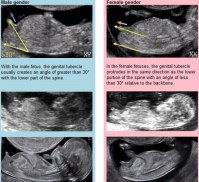

Nub Theory Come Determinare Il Sesso Del Bambino Con Ecografia Gia A 11 Settimane

Chiarimenti Nub Theory Predizione Sesso

Determinazione Del Sesso Fetale In Gravidanza Come E Quando E Possibile Saperlo La Medicina In Uno Scatto